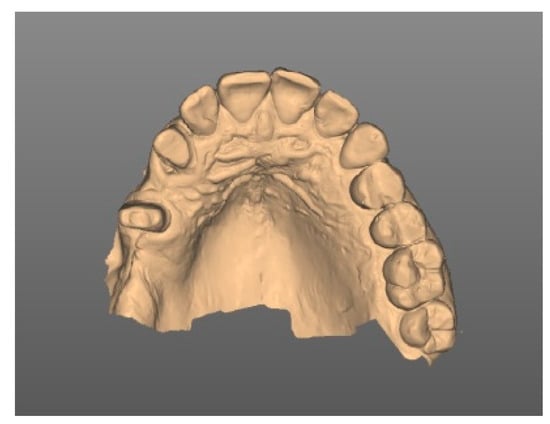

| Diagnostic | Intraoral scans |

| Planning | Digital set-up |

| Digital prosthetically driven implant planning | |